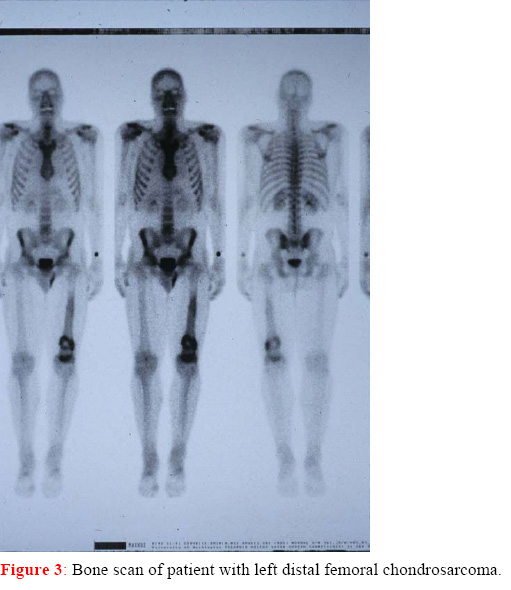

A bone scan of the entire body can also be helpful in differentiating between benign and malignant tumors,

and in identifying whether more than one bone is involved (although multiple bone involvement is rare with

chondrosarcomas). This test works by injecting a small amount of radioactive material into the blood stream

and taking images using a gamma camera to detect uptake of radioactive material. Lesions demonstrated on

bone scan can be compared to internal controls (Murphey et al., 1996). Those lesions demonstrating a

higher degree of uptake are more likely to be of higher histologic grade. However, most Enchondromas and

Exostoses / Osteochondroma exhibit some radioisotope uptake, and some will erroneously

appear as malignancy. Great caution should therefore be used in drawing conclusions from bone scan

results, but these results can add to the overall picture, and better inform the decision making process.